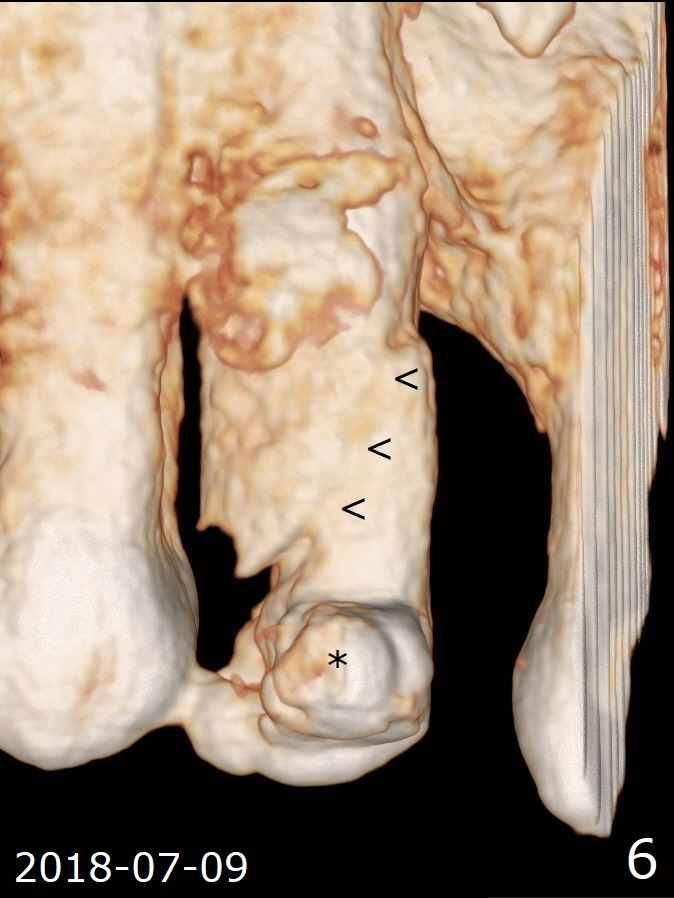

A 62-year-old man had traumatic root fracture at #6 in his teen. The tooth remained asymptomatic until his fifties. Following root canal therapy (Fig.1), the tooth is orthodontically extruded (~ 5 years, Fig.2 (*: bracket)) with apparent disappearance of the infection. The bone distal to #7 seems to increase in height (Fig.3, as compared to Fig.1) and in density (Fig.4). Bone graft could be placed for regeneration with PRF or GEM21S (Fig.5 red (between #6 and 7), pink (buccal to #7 or coronal to the fracture line) circles). With extrusion, the oblique fracture line is more than half or two third supragingival (Fig.6). In spite of severe bone loss, exostosis is present (Fig.7 (mesiobuccal view) E) so that bone graft could be placed palatal to it (Fig.8 red). In case the tooth is non-salvageable, immediate implant will be placed with guide (Fig.9,10). Move lingual button as apical as possible (Fig.12) and make occlusal clearance. Continue extrusion until all of the crack is exposed without deep pocket.